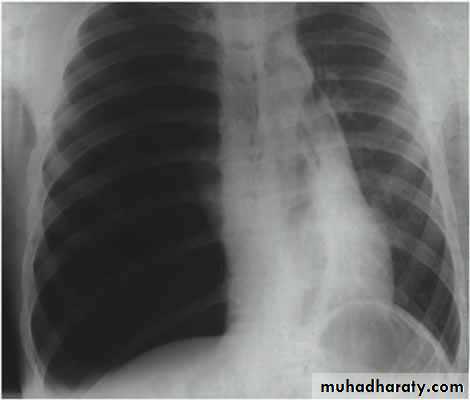

Tension Pnenmothorax

What is the difference??CT scan